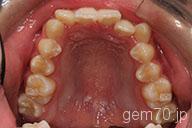

症状:叢生装置:セラミックブラケット | 非抜歯(歯を抜かない)世代:中学生

主訴)歯のでこぼこ

診断)叢生

年齢)14歳

使用装置)マルチブラケット装置

治療方法)非抜歯(歯を抜かない)

治療期間) 2年4ヵ月 通院回数 27回